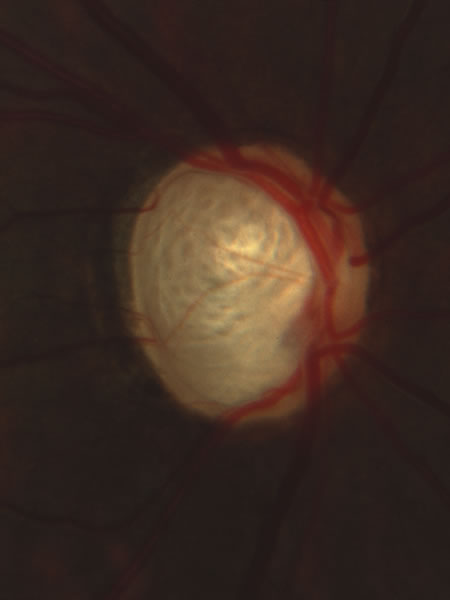

Usually all other forms of optic nerve disease (and inner retinal disease) produce simple atropy of the disc without cupping (Figs. 34 to 36), but occasional cases of cupping have been seen with anterior ischemic optic neuropathy, particularly due to giant cell arteritis (Figs. 37 and 38).

Fig. 37. Swollen optic nerve superiorly during anterior ischemic optic neuropathy caused by giant cell arteritis.

Fig. 38. Same eye after resolution of the attack, with excavation extending to the superior rim of the disc, mimicking the appearance of glaucomatous cupping.